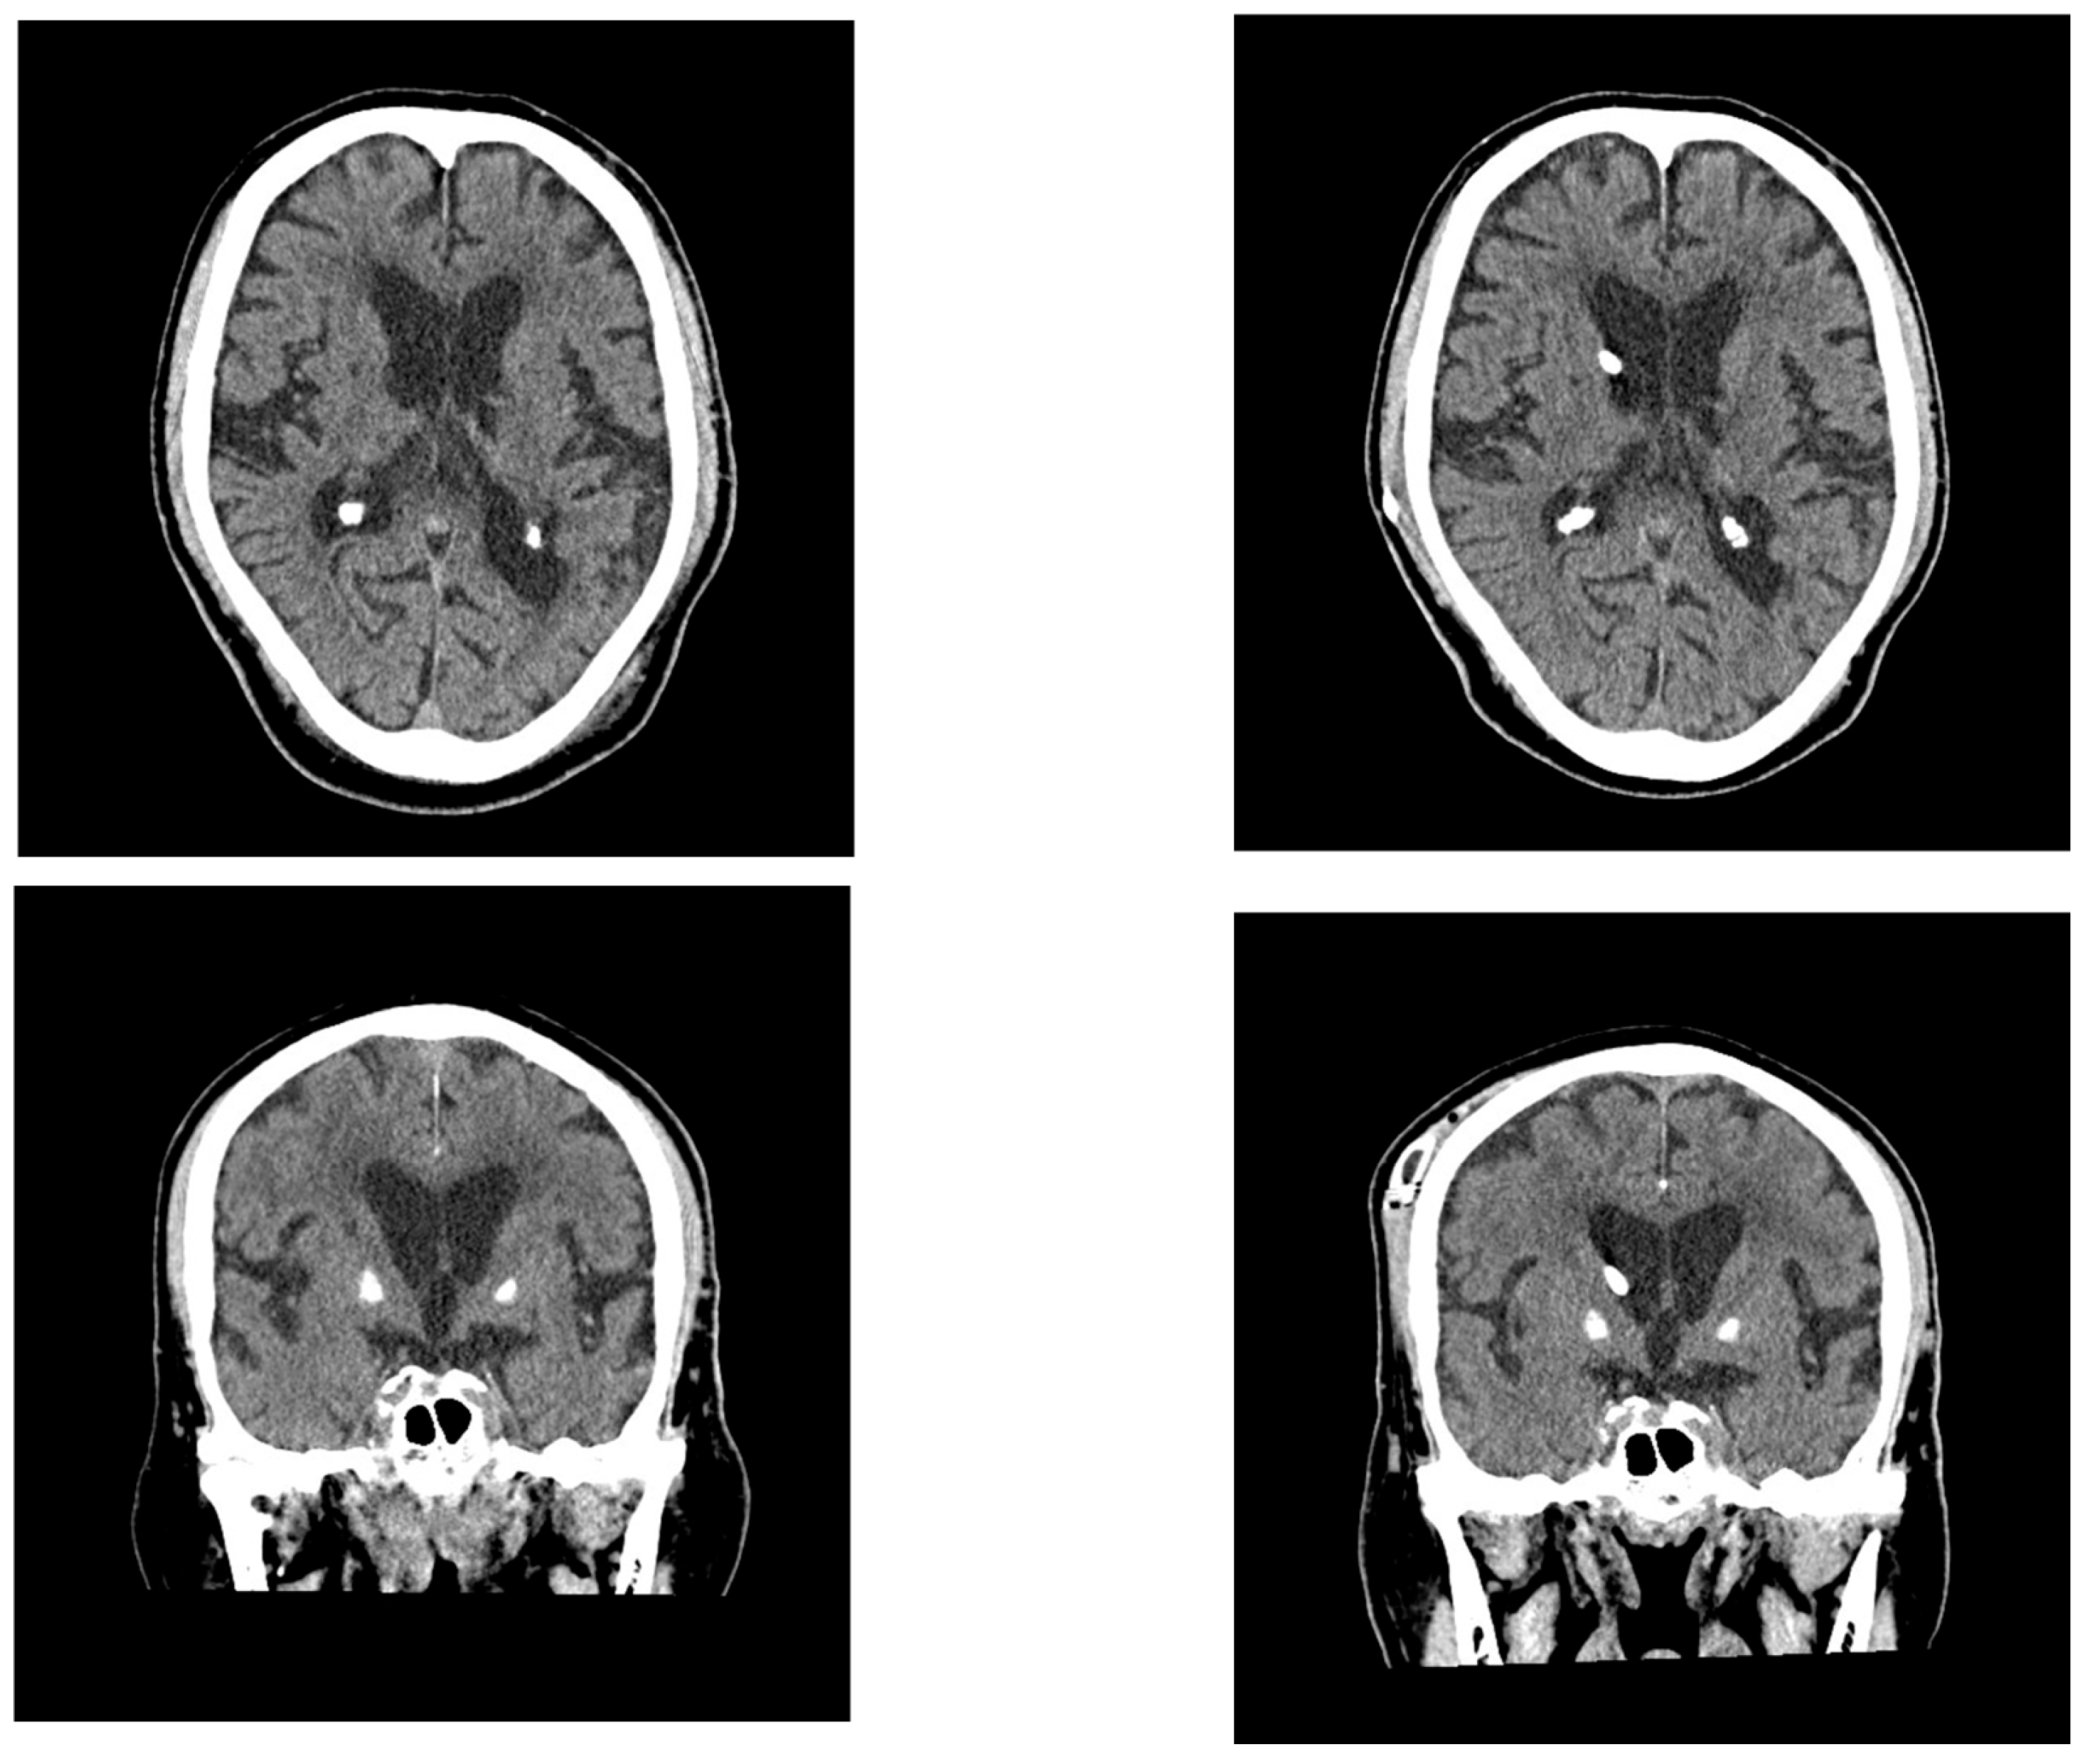

2.1. Case 1

2.2. Case 2